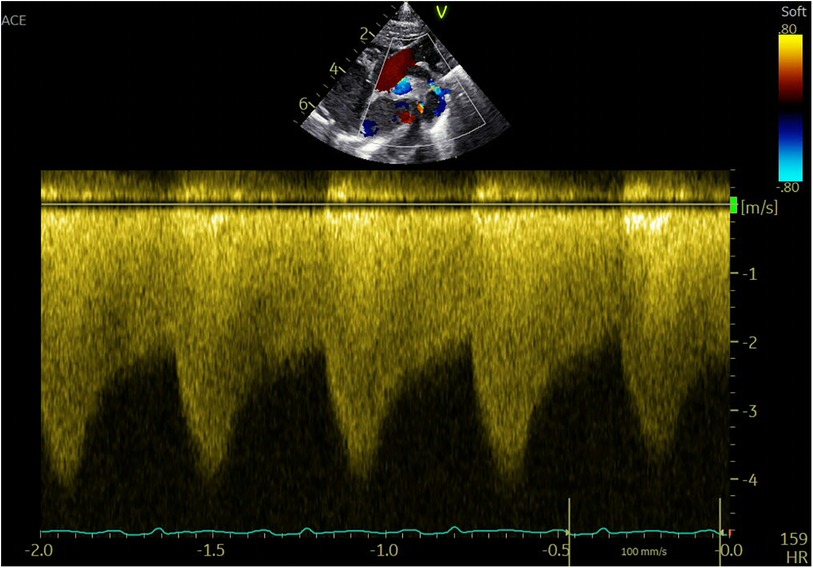

Imaging studies included a chest x-ray showing cardiomegaly and pulmonary congestion, followed by echocardiography, which identified a persistent fifth aortic arch (PFAA) with coarctation (narrowest diameter: 5 mm), an interrupted fourth aortic arch (Figure 1). Color Doppler demonstrating turbulent flow at the coarctation site (peak velocity: 4.1 m/s) (Figure 2). A patent ductus arteriosus (PDA; 3 mm) located between the proximal descending aorta and the pulmonary artery bifurcation, and an atrial septal defect (ASD; 6 × 8 mm), accompanied by reduced left ventricular systolic function (ejection fraction: 49%). Cardiac CT (Figures 3, 4) further confirmed the anatomical details, including a 12 mm gap in the fourth aortic arch and the PFAA's aberrant course.

Ultrasound Doppler echocardiogram showing blood flow velocity in the heart. The top section displays red and blue color-coded Doppler imaging, while the bottom section shows a graph with velocity scales, ranging from negative two to zero point zero.

Figure 2. Color Doppler demonstrating turbulent flow at the coarctation site (peak velocity: 4.1 m/s).